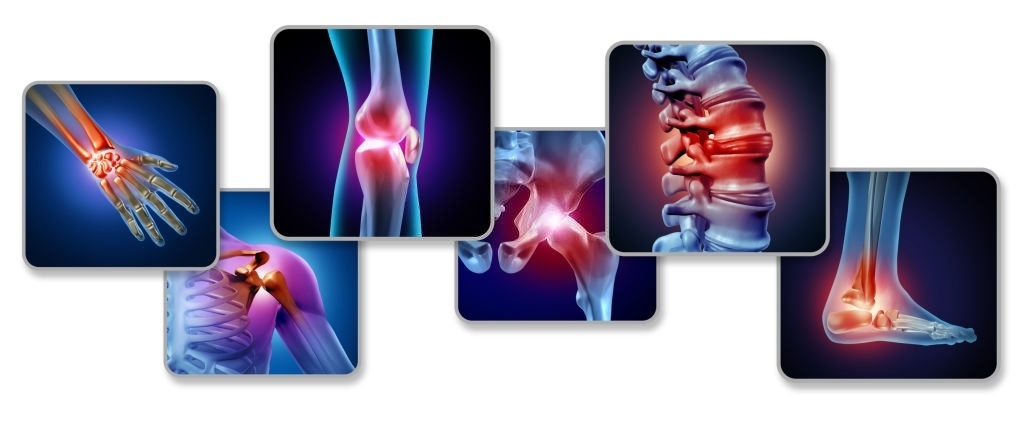

ويميل التهاب المفاصل الروماتويدي المبكر إلى مهاجمة المفاصل الأصغر في البداية والتأثير عليها، حيث تربط المفاصل اليدين بالأصابع وأصابع القدمين بالقدمين. وبمجرد أن يبدأ المرض في التقدم، تنتشر الأعراض إلى الرسغين والركبتين والكاحلين والوركين والكتفين. وقد تختلف الأعراض في شدتها وقد تأتي وتختفي.